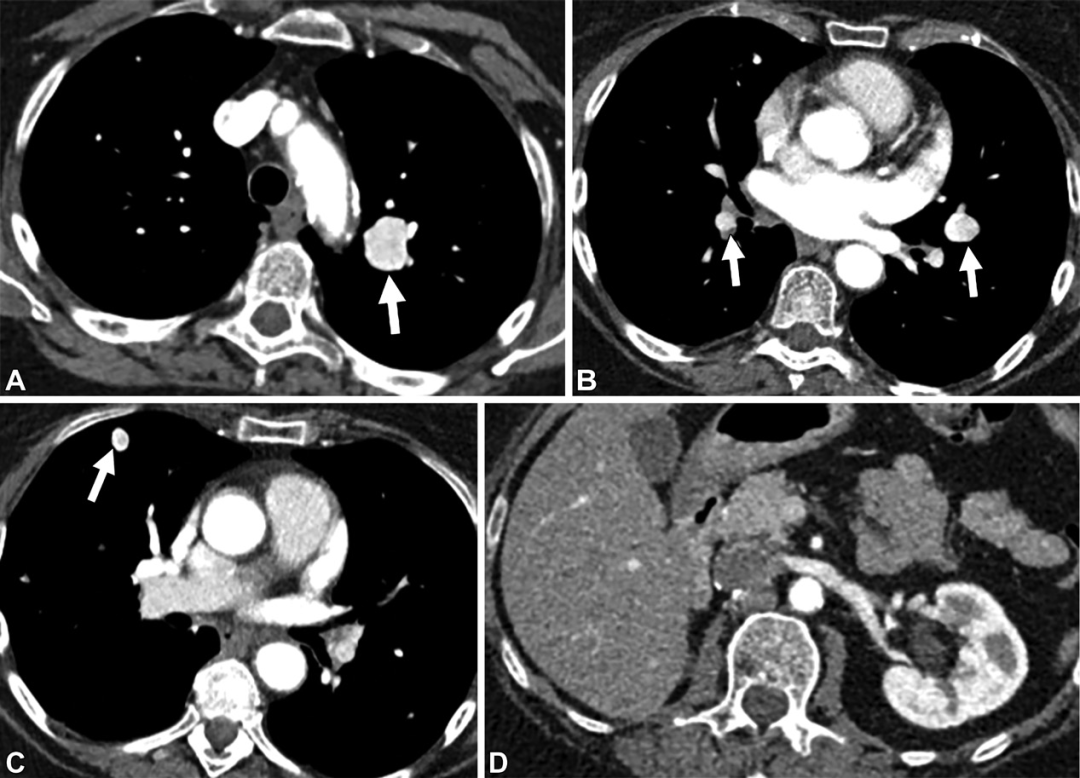

多发强化病变。47岁女性。(A至C)轴位CT增强图,可见肺内多发强化病变,与血管邻近。未见供血动脉及引流静脉。(D)腹部CT增强图,可见有肾切除术后改变。符合肾细胞癌的富血供转移。